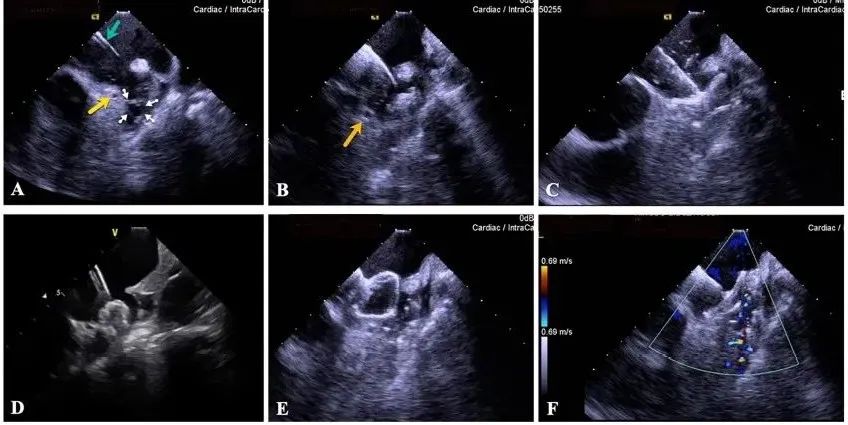

一種與心導(dǎo)管檢查相結(jié)合的超聲心動圖診斷新興技術(shù),通過將超聲探頭置于心腔內(nèi)部,發(fā)射并接收超聲信號,來精確獲取心臟解剖結(jié)構(gòu)、心臟血流動力學(xué)等信息的實時成像。與其他影像技術(shù)相比,ICE技術(shù)具有操作簡單、無輻射、安全性高、手術(shù)效率高、實用等優(yōu)勢,ICE在很大程度上有望取代經(jīng)食道超聲心動圖(TEE),成為電生理和結(jié)構(gòu)性心臟病領(lǐng)域的理想成像方式。

目前ICE技術(shù)已被應(yīng)用于左心耳封堵、房顫射頻消融、二尖瓣成形、房間隔缺損封堵等多種心臟介入手術(shù),應(yīng)用場景主要圍繞臟電生理、結(jié)構(gòu)性心臟病等領(lǐng)域,目前以電生理應(yīng)用為主。數(shù)據(jù)顯示,我國結(jié)構(gòu)性心臟病介入器械市場規(guī)模已從2017年的4億元增長至2021年的20億元,年復(fù)合增長率達48.3%;預(yù)計到2025年,該市場規(guī)模將達到104億元,可以預(yù)見ICE市場規(guī)模也將同步高速增長,未來市場發(fā)展空間廣闊。